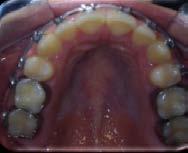

Figura 7 Cone-beam de control de la zona más distal del primer cuadrante donde se planifica un implante extracorto

Para elaborar la planificación de los implantes a colocar se realiza en primera instancia un TAC, observándose en el mismo que existe un déficit de altura en todo el maxilar superior.

Todos los dientes conservados reciben un mantenimiento periodontal riguroso (Figura 4-6). Transcurridos 2 meses, comenzamos con la rehabilitación del maxilar superior mediante implantes. Durante este tiempo se lleva a cabo la inserción y rehabilitación provisional mediante prótesis de carga inmediata de la mandíbula. Para elaborar la planificación de los implantes a colocar se realiza en primera instancia un TAC, observándose en el mismo que existe un déficit de altura en todo el maxilar superior, siendo más acusada la atrofia en altura en la zona de los molares. En el primer cuadrante, tenemos una altura ósea de 5.5 mm por lo que podemos planificar la colocación de un implante extracorto (5.5 mm de longitud y 5.5 mm de diámetro) con elevación de seno transcrestal (Figura 7). En el segundo cuadrante, existe una atrofia ósea en altura mucho mayor con menos de 1 mm de altura, existiendo áreas donde se produce una ruptura